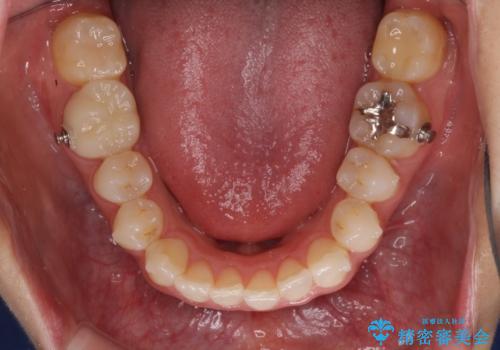

矯正治療により下顎前歯を整列させたため、上顎前歯のセラミックブリッジを補綴することで口元を少し下げることができました。

ヒトの目線がいつも口元に向けられているように感じることがなくなり、患者様には大変満足していただきました。